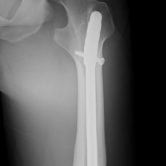

Röntgenbilder